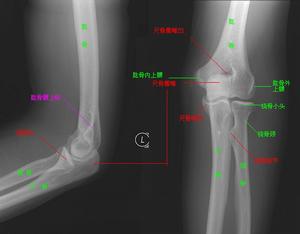

本病最常見的檢查方法為X線檢查,也是本病的診斷依據,其X線特點如下:

⑴肱橈關節正常,肘關節正位及側位片均顯示橈骨縱軸通過肱骨小頭。

⑵尺橈關係不變,即上尺橈關係正常。

⑶肱骨與尺橈骨排列失常,往往是尺橈骨帶一乾骺端骨折片或肱骨外髁移向後上方。